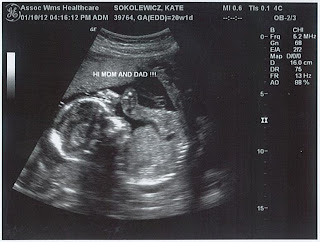

Here are some ultrasound pictures from our 20-week check-up:

"Hi mom & dad!"